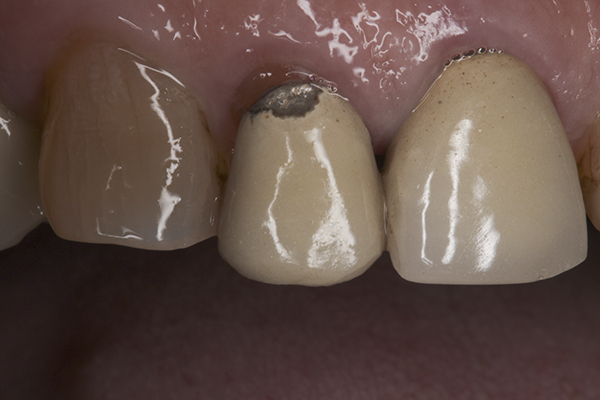

(12.) Preoperative right anterior, close-up view.

Figure 12

(13.) Preoperative anterior, close-up view.

Figure 13